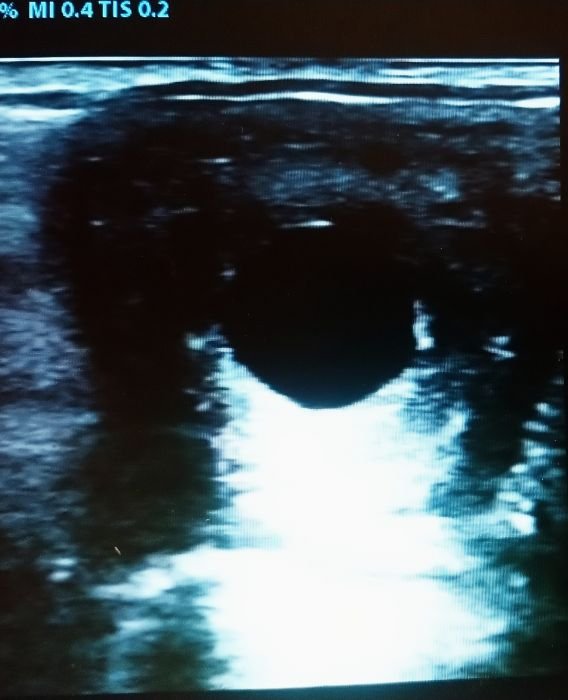

Folikulární vlna na vaječníku klisny

Dominantní folikul krátce před ovulací

Gravidita klisny 13. den

Říjová děloha klisny

Gravidita klisny 16. den